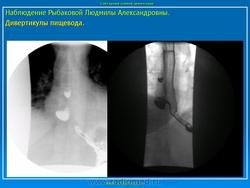

Клиническая картина, предварительный диагноз У большинства больных, особенно с небольшими дивертикулами, стойкие симптомы заболевания могут отсутствовать. Лишь эпизодически возникает дисфагия, чаще при поспешной еде, еде всухомятку. При дивертикулах больших размеров дисфагия возникает почти при каждом приеме пищи, в положении лежа может наблюдаться регургитация (обратное затекание) содержимого дивертикула в пищевод и глотку, срыгивание. Эти больные могут отмечать неприятный запах (вследствие разложения задержавшихся в пищеводе пищевых остатков). Основное значение для диагностики дивертикула имеет контрастное рентгенологическое исследование, при котором устанавливают дивертикул, определяют его размеры, форму, наличие или отсутствие в нем контрастной массы и пищевых остатков. Небольшие дивертикулы средней и нижней трети пищевода, в которых не задерживается контрастная масса, лучше выявляются при рентгенологическом исследовании пищевода в положении больного лежа. Небольшие бессимптомно протекающие дивертикулы часто являются случайной рентгенологической находкой при контрастном рентгенологическом исследовании, проводимом по другому поводу. Дивертикулы, соединяющиеся с пищеводом широким сообщением, выявляют при эзофагоскопии. Со временем дивертикулы нередко увеличиваются в размерах. При плохом опорожнении дивертикула (при мешкообразной форме, с дном, расположенным значительно ниже шейки дивертикула) в нем задерживается пища (особенно плохо разжеванные куски), которая может разлагаться; велика опасность возникновения дивертикулита, а затем - медиастинита. В дивертикулите могут задерживаться и проглоченные инородные тела (кусочки куриной или рыбьей кости и др.).

У большинства больных, особенно с небольшими дивертикулами, стойкие симптомы заболевания могут отсутствовать. Лишь эпизодически возникает дисфагия, чаще при поспешной еде, еде всухомятку. При дивертикулах больших размеров дисфагия возникает почти при каждом приеме пищи, в положении лежа может наблюдаться регургитация (обратное затекание) содержимого дивертикула в пищевод и глотку, срыгивание. Эти больные могут отмечать неприятный запах (вследствие разложения задержавшихся в пищеводе пищевых остатков). Основное значение для диагностики дивертикула имеет контрастное рентгенологическое исследование, при котором устанавливают дивертикул, определяют его размеры, форму, наличие или отсутствие в нем контрастной массы и пищевых остатков. Небольшие дивертикулы средней и нижней трети пищевода, в которых не задерживается контрастная масса, лучше выявляются при рентгенологическом исследовании пищевода в положении больного лежа. Небольшие бессимптомно протекающие дивертикулы часто являются случайной рентгенологической находкой при контрастном рентгенологическом исследовании, проводимом по другому поводу. Дивертикулы, соединяющиеся с пищеводом широким сообщением, выявляют при эзофагоскопии. Со временем дивертикулы нередко увеличиваются в размерах. При плохом опорожнении дивертикула (при мешкообразной форме, с дном, расположенным значительно ниже шейки дивертикула) в нем задерживается пища (особенно плохо разжеванные куски), которая может разлагаться; велика опасность возникновения дивертикулита, а затем - медиастинита. В дивертикулите могут задерживаться и проглоченные инородные тела (кусочки куриной или рыбьей кости и др.).